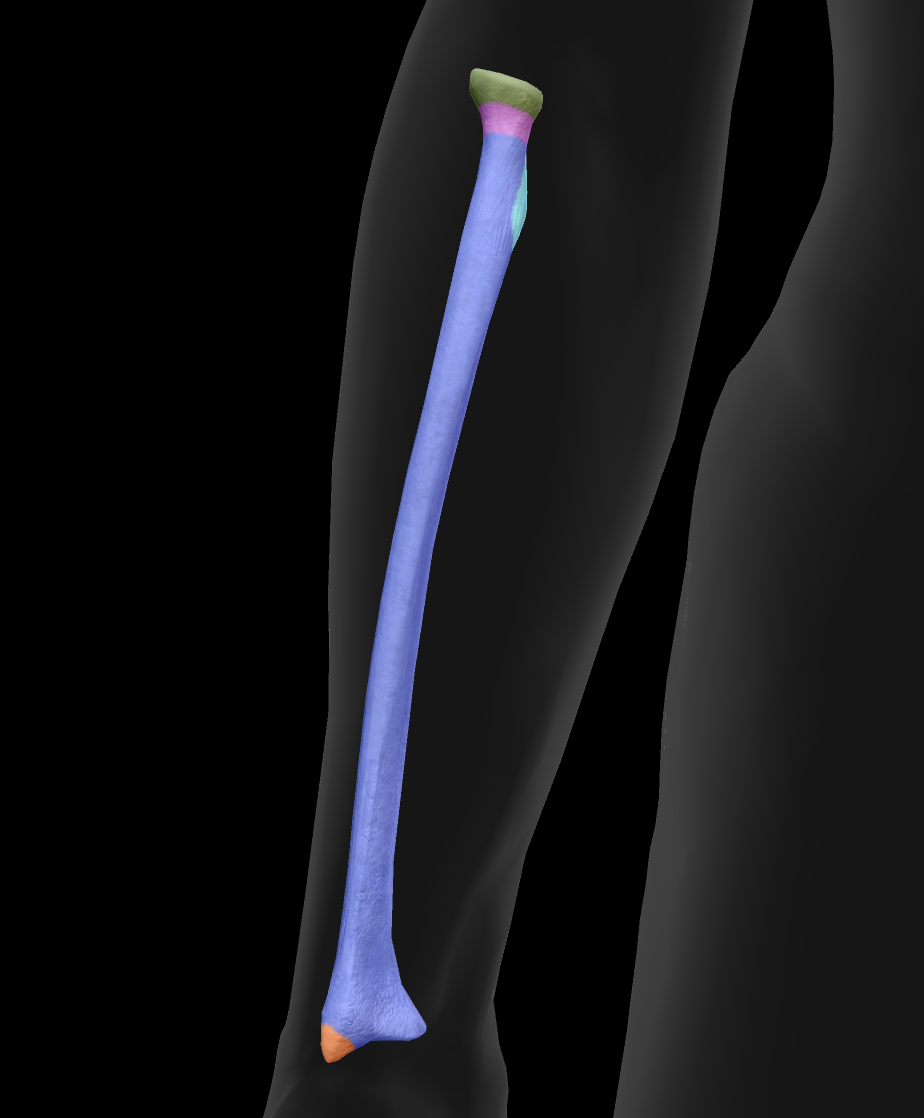

What is this bone?

radius

What is this boney landmark?

head

What is this boney landmark?

neck

What is this boney landmark?

radial tuberosity

What is this boney landmark?

shaft

What is this boney landmark?

radial styloid process

What is this boney landmark?

ulnar notch

What is this boney landmark?

lister’s tubercle